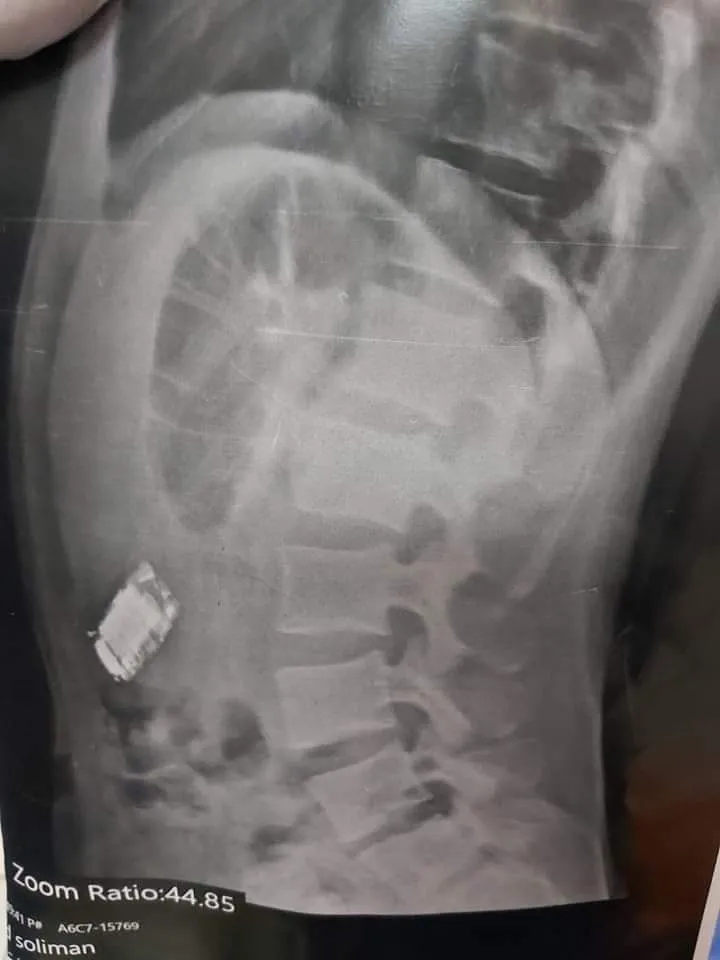

نجح أطباء مستشفى شبين الكوم التعليمي بمحافظة المنوفية فى استخراج هاتف محمول من أحشاء شاب، وكان الهاتف ملفوف بكيس بلاستيك، وتمت العمليه بنجاح، تحت إشراف الأستاذ الدكتور محمد طاحون مدير عام مستشفى شبين الكوم التعليمي.

البداية كانت بمجيء مريض  ابتلع محمول صغير يبلغ من العمر 20 عاما، قام الفريق الطبي بعمل الفحوصات والتحاليل اللازمة بمستشفى شبين الكوم التعليمي، وبعد التأكد من وجود الهاتف، تم تحضير المريض لدخول العمليات.

وعلى الفور، توجه فريق من أطباء مناظير الجهاز الهضمي على أعلى مستوى من المهارة تحت رئاسة الأستاذ الدكتور عماد الديب، والأستاذ الدكتور أحمد صلاح رئيس قسم المناظير، وأطباء التخدير والكبد والأنف الأذن بالمستشفى تحسبا لأي طارىء.